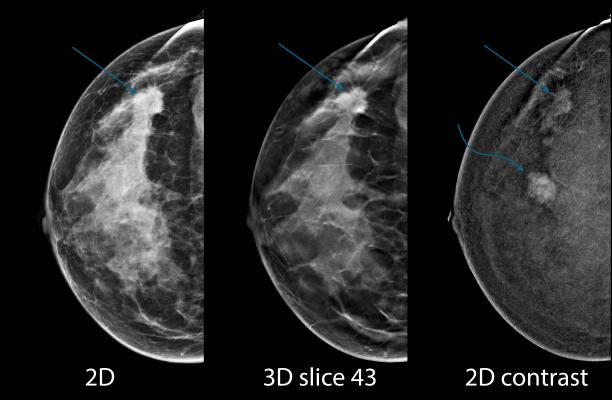

Bahl and colleagues at MGH studied the use of a machine learning tool to identify high-risk lesions that are at low risk for upgrade to cancer. The study resulted from a close collaboration between researchers at the Massachusetts Institute of Technology's (MIT) Computer Science and Artificial Intelligence Laboratory in Cambridge, Mass., and breast imaging experts at MGH.

Machine learning is a type of artificial intelligence in which a model automatically learns and improves based on previous experiences. The model developed by researchers analyzed traditional risk factors such as patient age and lesion histology, along with several unique features, including words that appear in the text from the biopsy pathology report. The researchers trained the model on a group of patients with biopsy-proven high-risk lesions who had surgery or at least two-year imaging follow-up. Of the 1,006 high-risk lesions identified, 115, or 11 percent, were upgraded to cancer.

After training the machine learning model on two-thirds of the high-risk lesions, the researchers tested it on the remaining 335 lesions. The model correctly predicted 37 of the 38 lesions, or 97 percent, that were upgraded to cancer. The researchers also found that use of the model would have helped avoid almost one-third of benign surgeries.